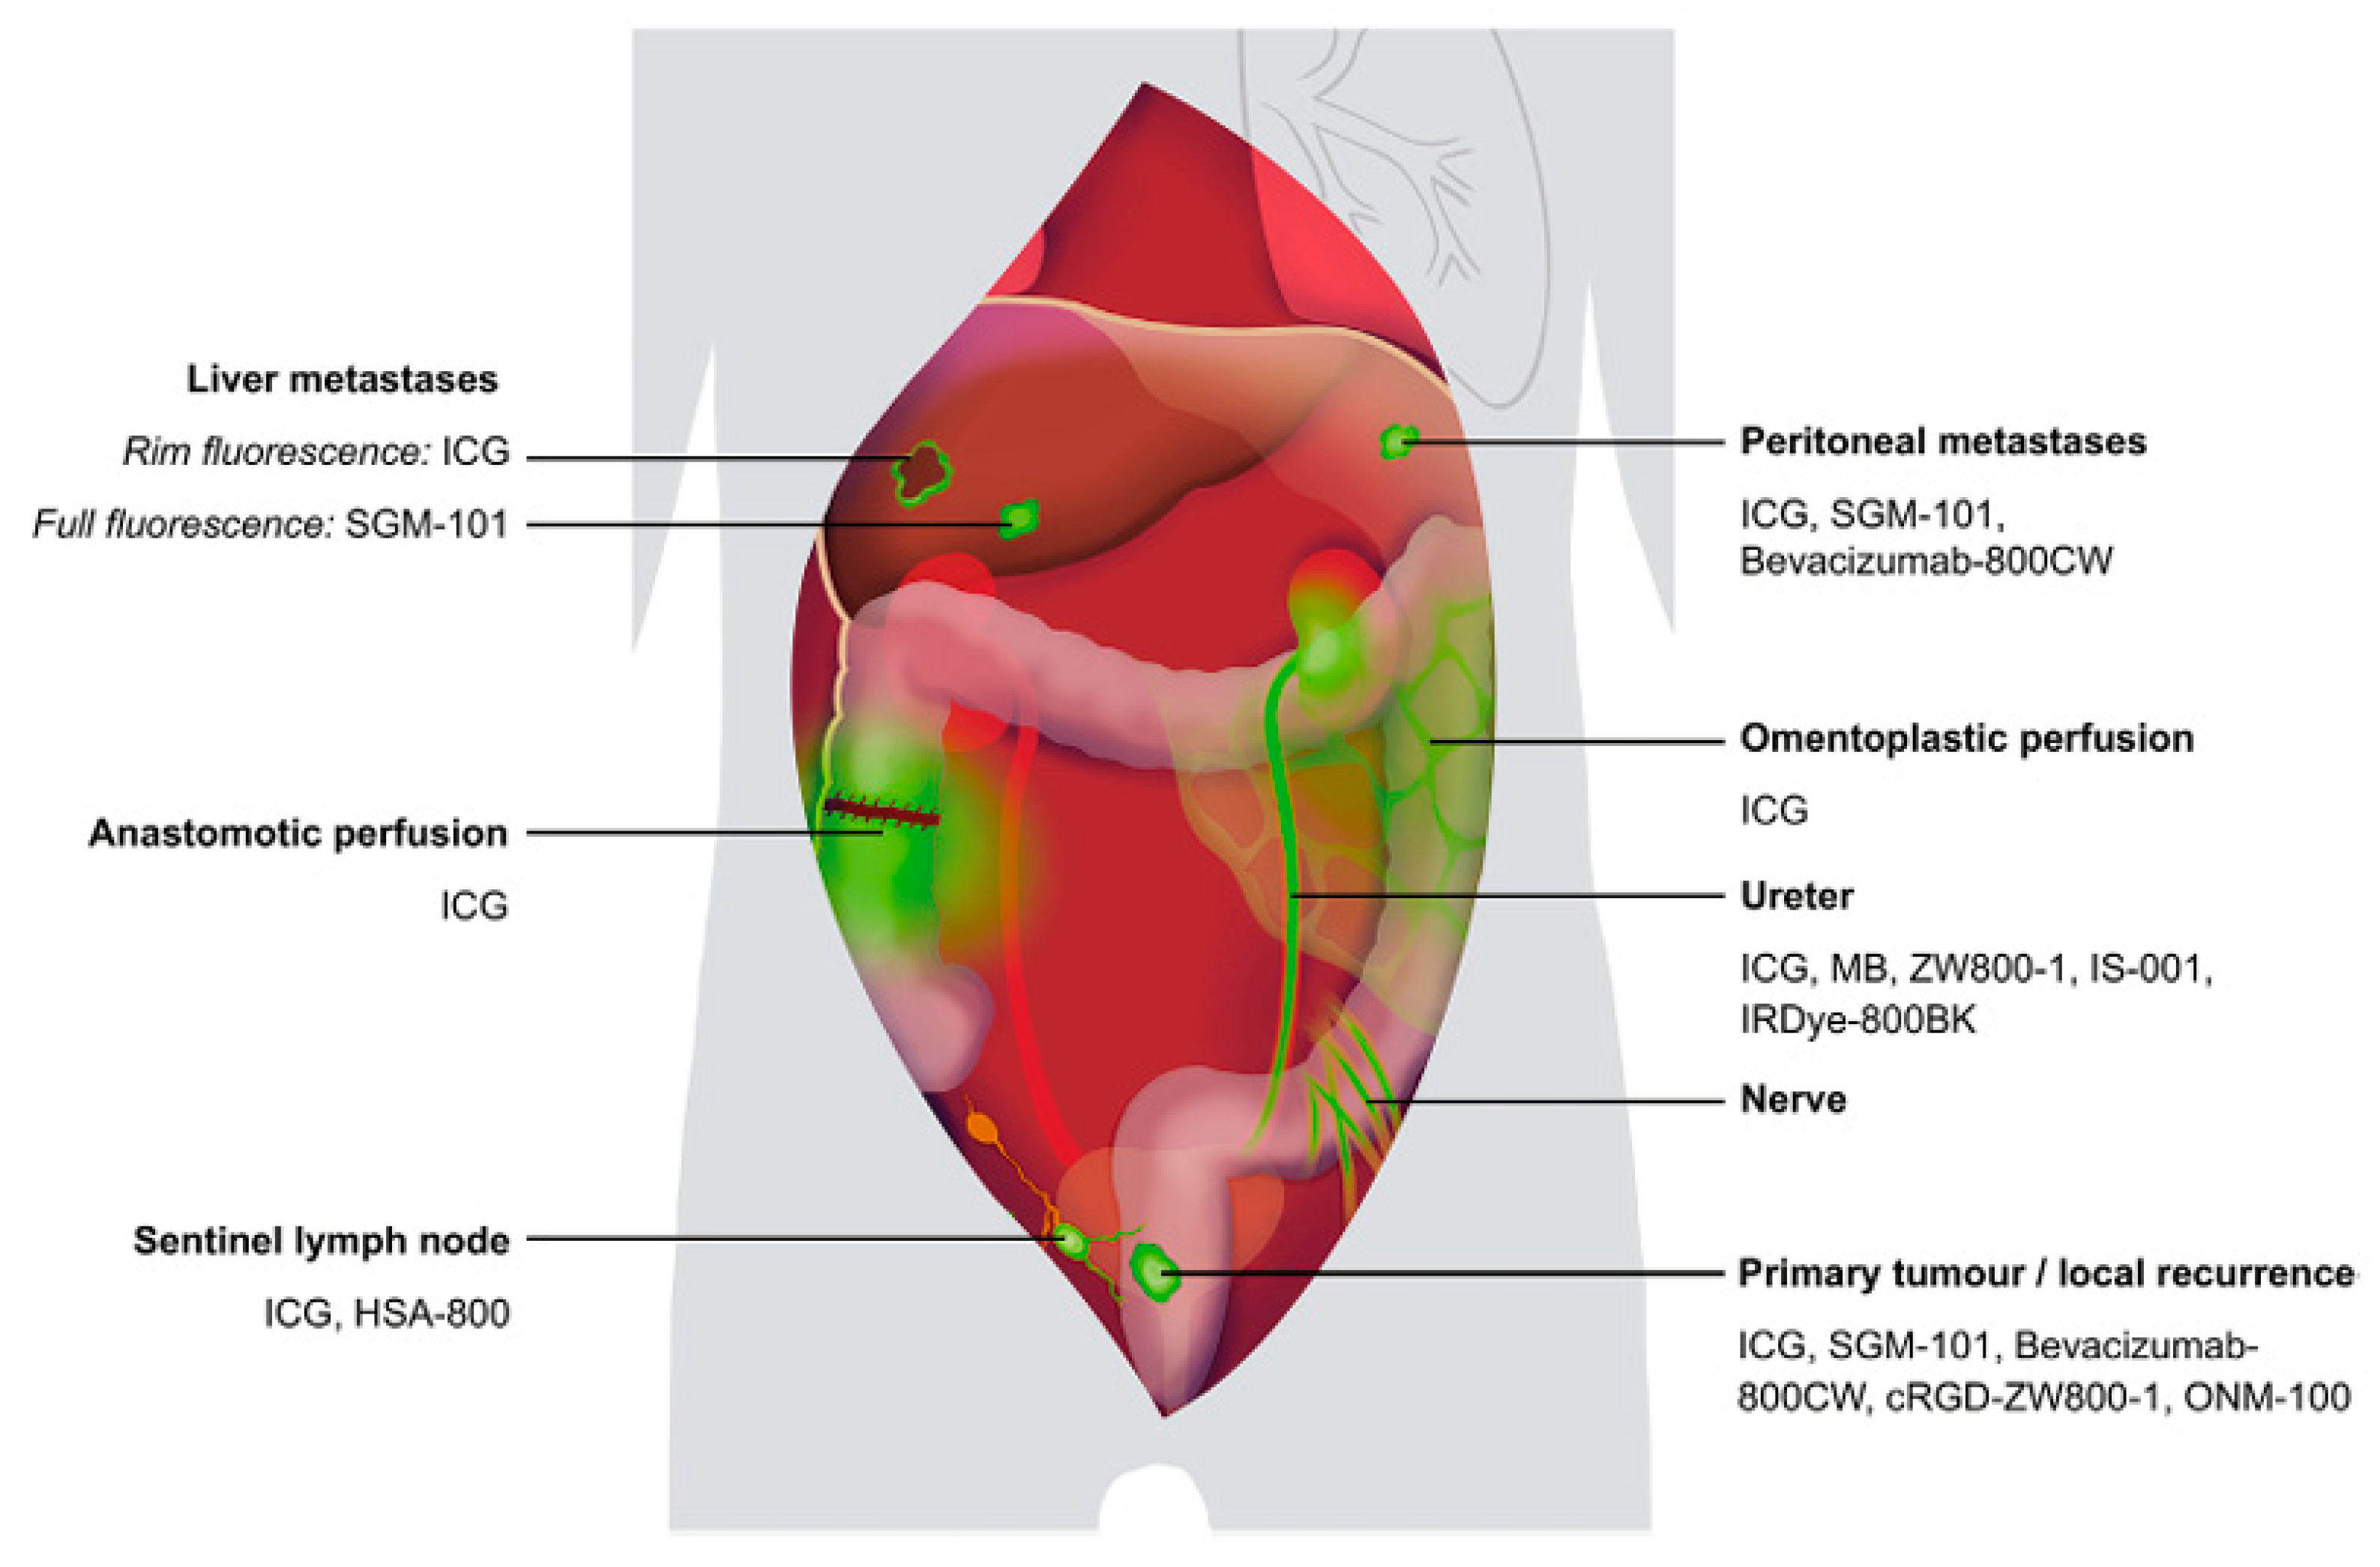

- Galema, H.A.; Meijer, R.P.J.; Lauwerends, L.J.; Verhoef, C.; Burggraaf, J.; Vahrmeijer, A.L.; Hutteman, M.; Keereweer, S.; Hilling, D.E. Fluorescence-guided surgery in colorectal cancer; A review on clinical results and future perspectives. Eur. J. Surg. Oncol. 2022, 48, 810–821. [Google Scholar] [CrossRef]

- Qiu, W.; Liu, Y.; Zhao, W.; Mei, S.; Li, Y.; Liu, Q. Efficacy of ICG-guided bilateral lateral lymph node dissection in rectal cancer. Clin. Surg. Oncol. 2025, 4, 100079. [Google Scholar] [CrossRef]

| Near-Infrared Fluorescence (NIR) | Uses ICG or targeted agents for real-time visualization | Improves intraoperative nerve visibility | [41,53] |

| Targeted NIR Probes | Fluorophores conjugated to nerve-specific ligands (e.g., cRGD-ZW800-1) | Enhances selective nerve detection | [53] |